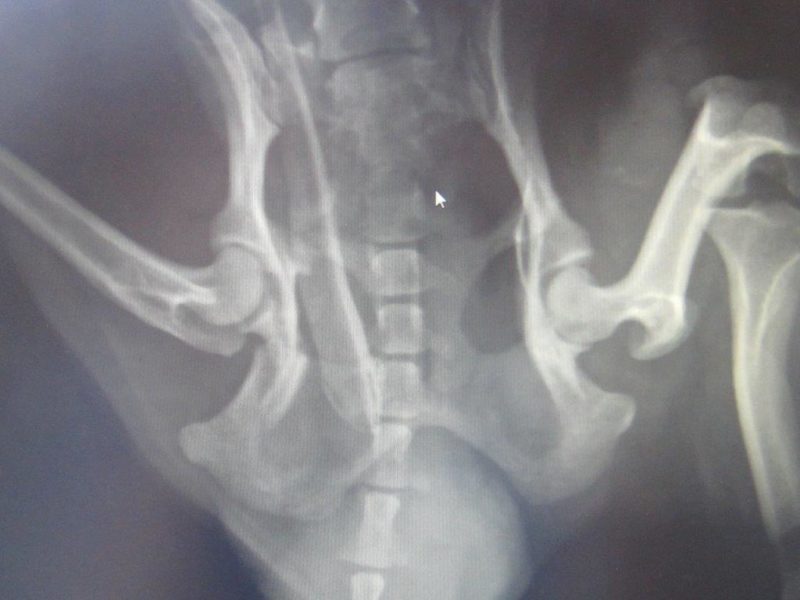

Auf der Röntgenaufnahme sind deutliche Weichteilschwellungen im Bereich des Beckens erkennbar. Die Harnblase ist fast vollkommen leer. Der rechte Beckenring im Bereich des Sitz- und Schambeins ist gebrochen, es sind auch kleinere Fragmentstücke erkennbar (Bild 2). Um die Durchgängigkeit des Beckenrings zu eruieren, wurde eine rektale Untersuchung durchgeführt. Der Beckenboden war stark geschwollen ohne fühlbare Spitzen durch mögliche Knochensplitter, die Blutergüsse verringerten seinen Durchmesser nur geringgradig.